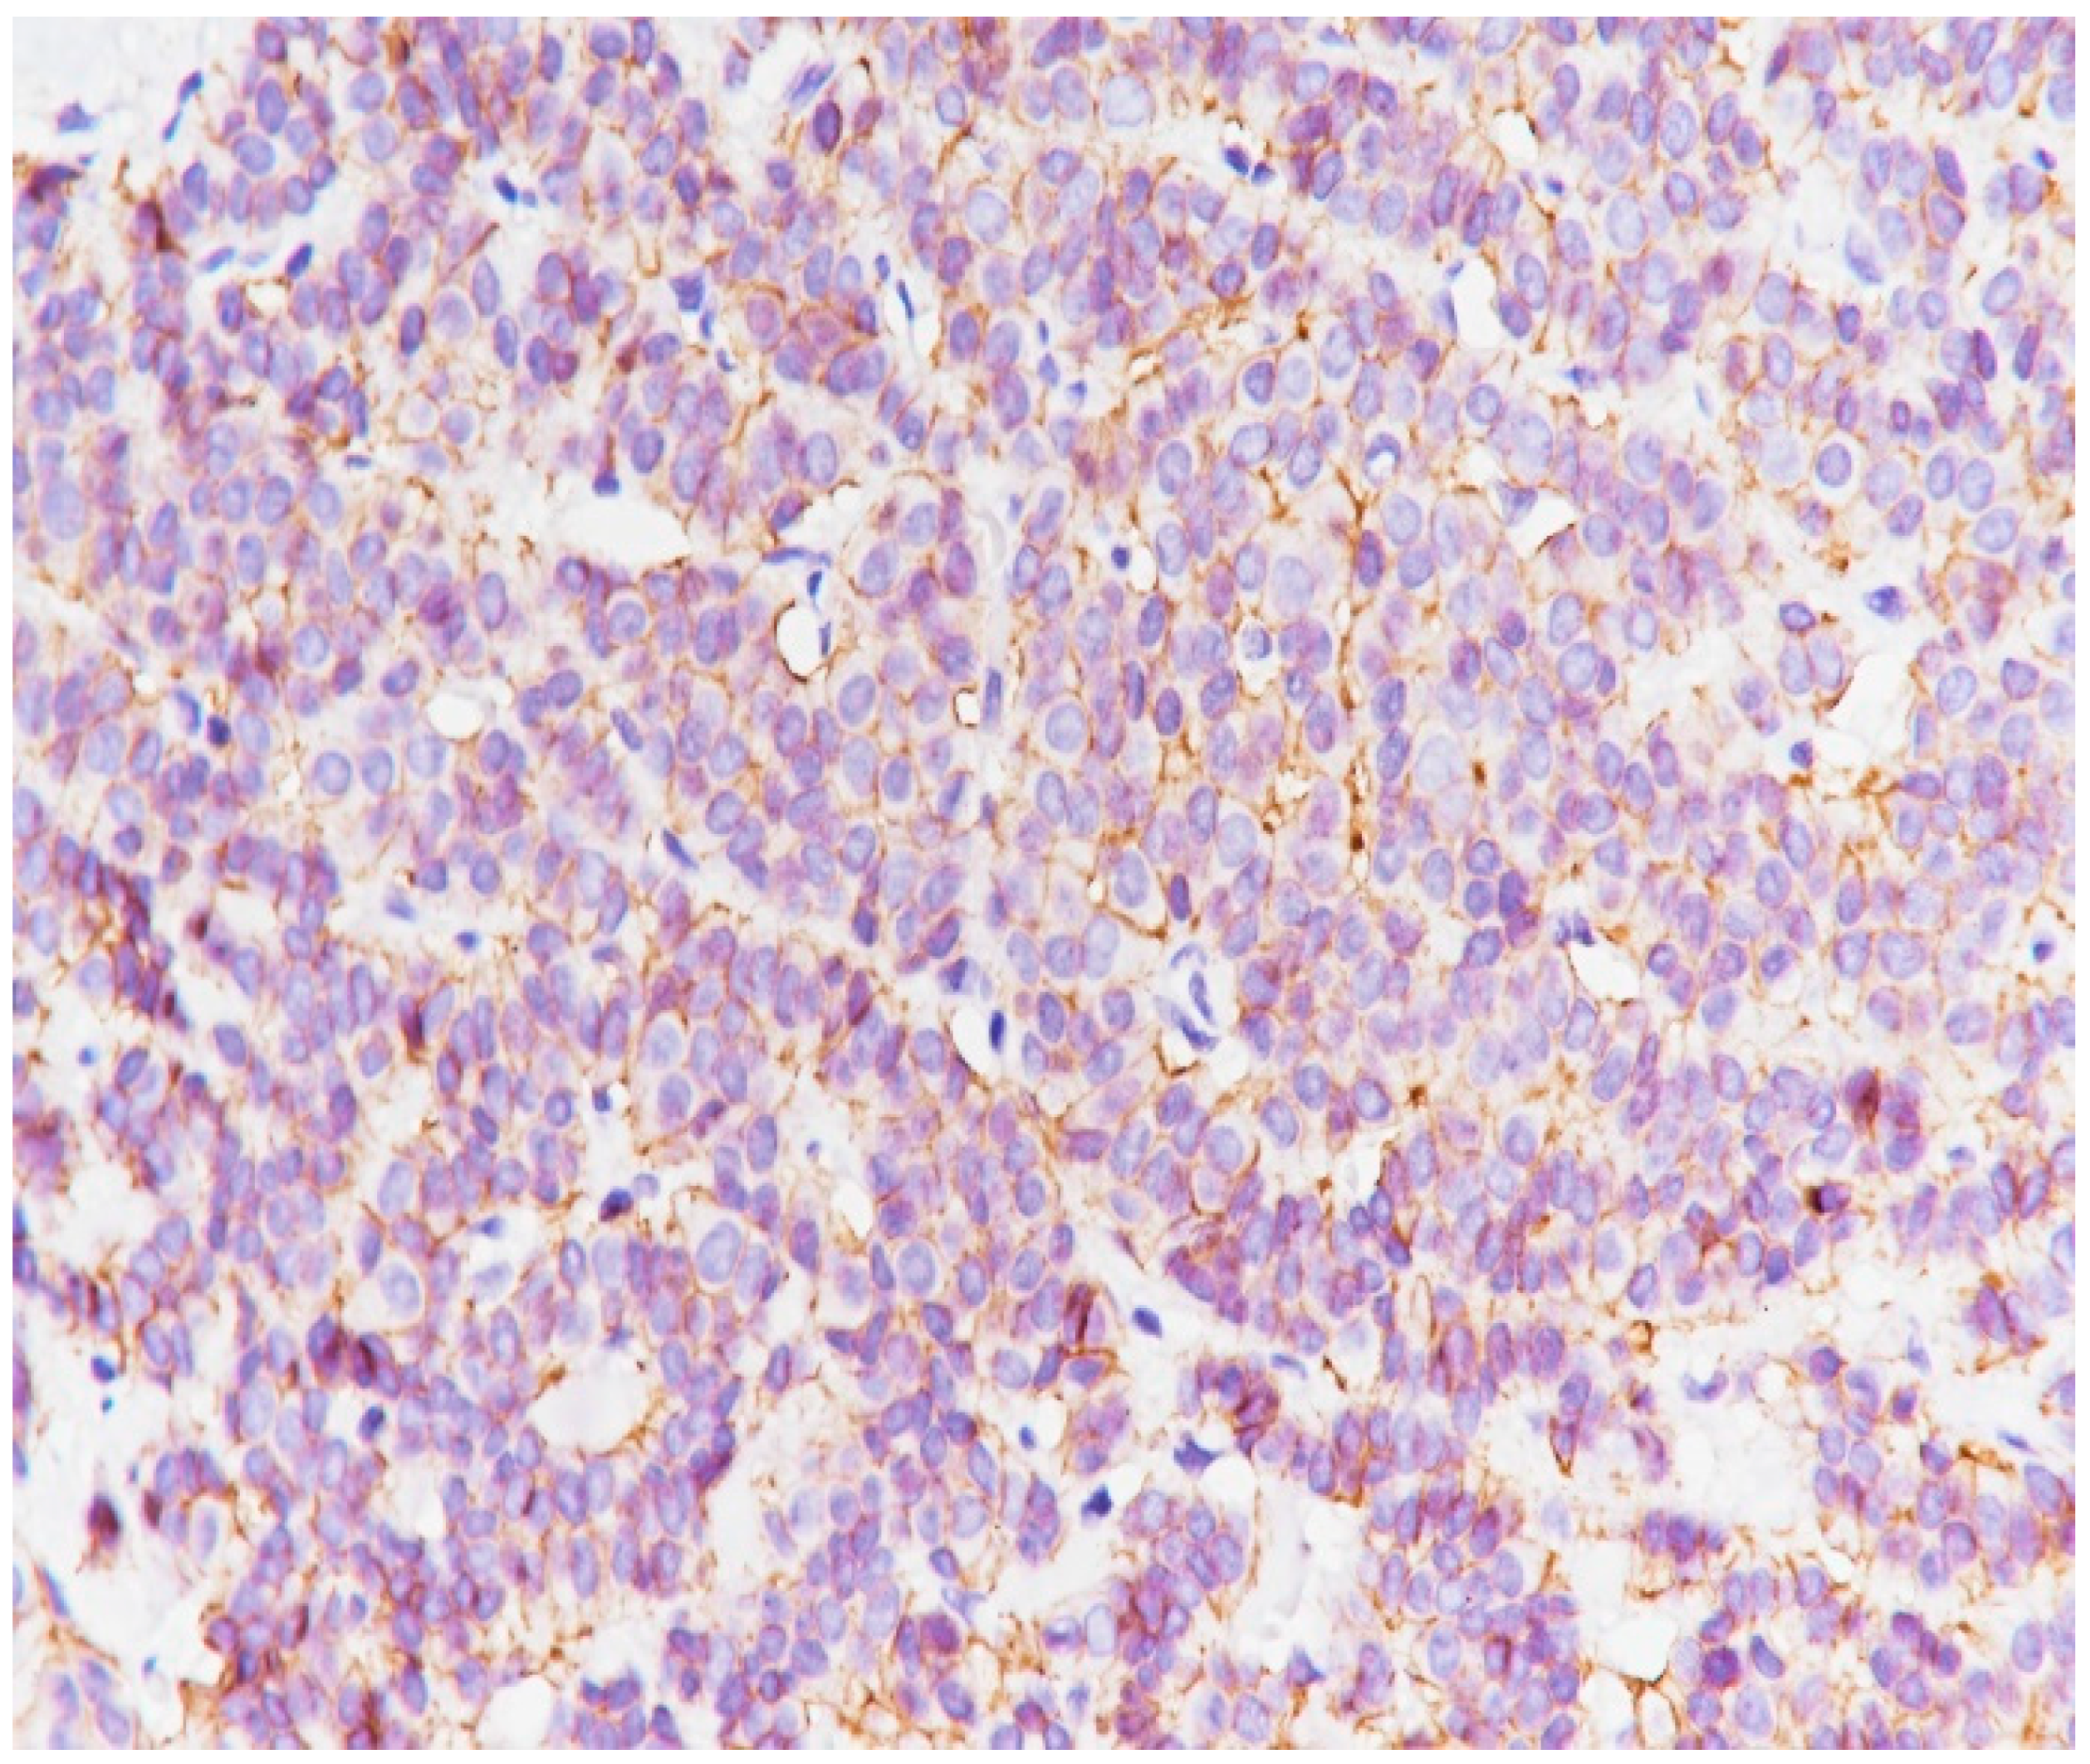

2. Case Presentation